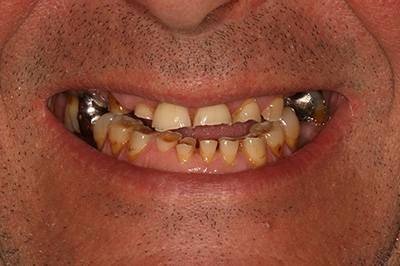

6. Eset

Nagymértékű fogkopás, erózió, csikorgatás a teljes rágóapparátust túlterhelve okoz reménytelennek tűnő helyzeteket.

Ebben az esetben implantátumok , koronák és hidak segítségével változtattunk a páciens fogainak érintkezésén. 6 hónapig ideiglenes hidakkal teszteltük a megváltoztatott harapási pozíciót. Ezután készültek el a végleges fix pótlások.